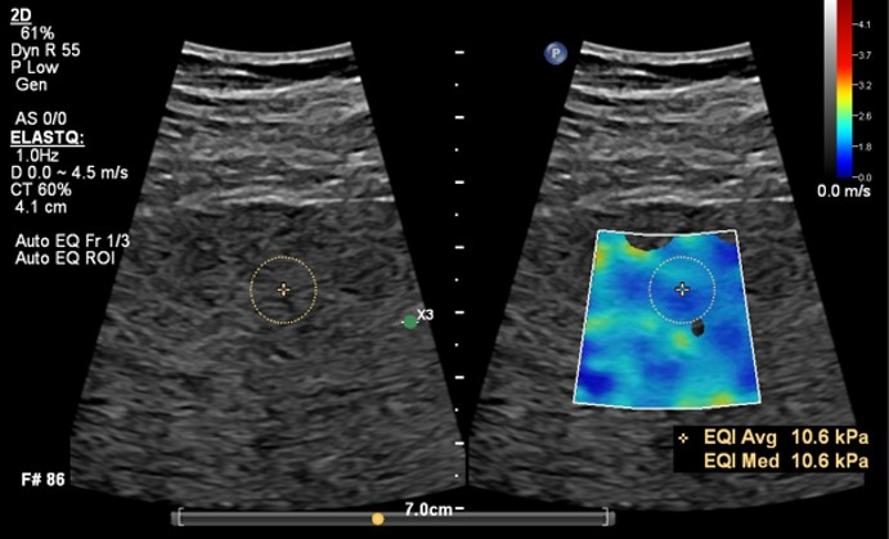

이러한 상황에서 필립스는 한층 기능이 강화된 초음파 제품 포트폴리오를 공개했다. 이번 업그레이드를 통해 간섬유화 검사 자동화 기능 ‘오토 엘라스트큐(Auto ElastQ)’와 고주파 프로브 ‘mL26-8’의 호환성을 범용 장비인 어피니티(Affiniti 50, 70) 라인업부터 고사양 장비인 에픽 엘리트(EPIQ Elite)까지 폭넓게 제공한다. 또한 심장 및 간 질환 진단 등 다양한 임상 분야에서 활용 가능한 워크플로우 개선 기능도 탑재했다.